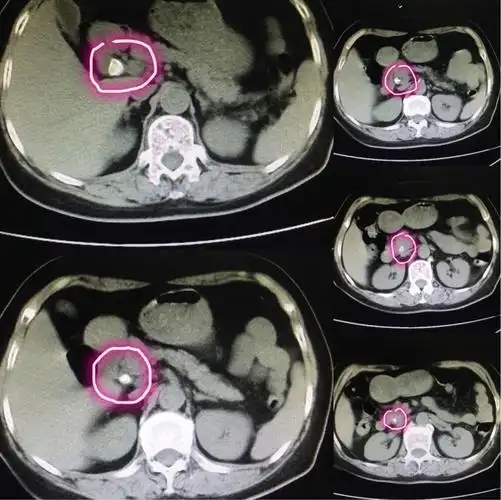

ct横断面可见结石自下而上填满胆总管.